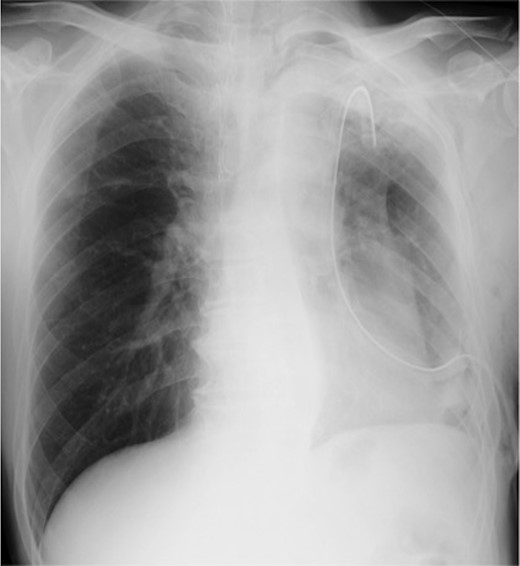

Left lower lobectomy and lymph node dissection were performed. Preoperative computed tomography imaging revealed multiple bullae in the apex of the left lung and very thin bullae walls (Fig. 2A). Concerned that the patient would develop a second primary lung cancer or pneumothorax in the future, we simultaneously performed a bullectomy for two bullae with a lobectomy (Fig. 2B). Because the patient’s lung was highly emphysematous, linear staplers with PGA felt (Endo GIA™ Reinforced Reload with Tri-Staple™ Technology, cartridge color: purple, MEDTRONIC, Tokyo, Japan) were used for the bullectomy. We confirmed the absence of bleeding in the thoracic cavity and completed the operation (Video 1). The drainage from the thoracic tube turned bloody beginning 1 h after the operation. The drainage volume increased, and 600 ml of bodily drainage was observed for 2 h after the drainage had turned bloody. A chest X-ray imaging examination was performed, which confirmed fluid accumulation in the left thoracic cavity (Fig. 3). Because the patient’s anemia had also progressed, as compared with preoperative measurements (preoperative hemoglobin, 12.8 g/dl; 3-h postoperative hemoglobin, 9.1 g/dl), we determined that sustained bleeding had occurred in the thoracic cavity; we subsequently decided to carry out a reoperation to perform hemostasis. No air leakage was observed during the period between both operations.

Chest X-ray image 2 h after the presence of bloody drainage from the thoracic tube caused suspicion of a left hemothorax.